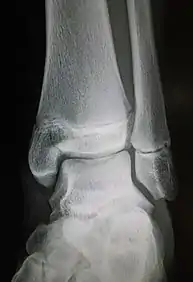

Ankle radiographs are used to detect widening of the tibiofibular syndesmosis or medial clear space. The medial clear space is the area between the talus of the ankle and the medial malleolus. Damage to the deltoid ligament and syndesmotic ligaments result in mortise instability, causing the talus to laterally shift and widen the medial clear space.[4][12] A clinical study, conducted in 2006 and published in the Journal of Bone and Joint Surgery, found that the medial clear space size of a normal ankle and an injured ankle measured at 4 millimetres and 5.4 millimetres in length respectively.[11] To confirm diagnosis, full-leg radiographs are used to inspect for fractures of the proximal fibula and widening of the interosseous clear space (or tibiofibular clear space). The interosseous clear space is the area between the medial side of the fibula and lateral side of the tibia. A peer-reviewed study, published in Injury in 2004, found that an interosseous clear space greater than 10 millimetres indicates diastasis of the syndesmotic ligaments.[4]